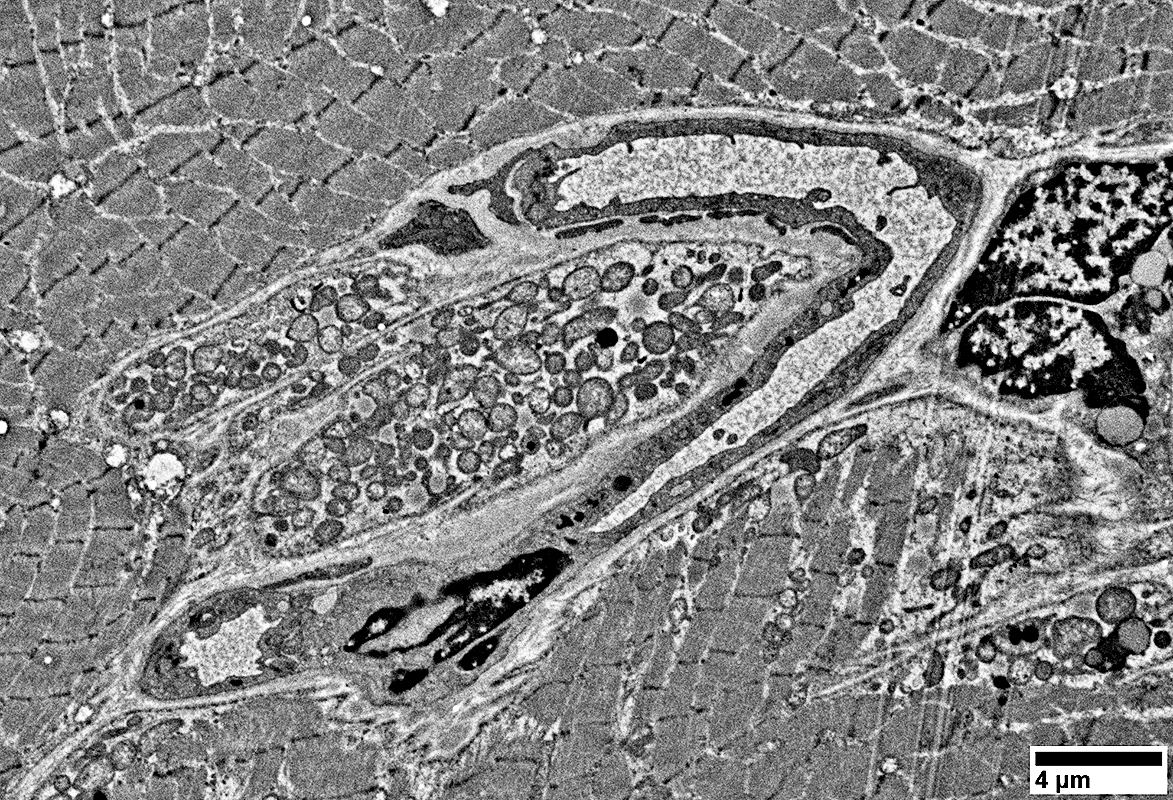

Endomysial capillaries

Endothelial cells with many vesicles

Large size

Thick wall

From: R Schmidt